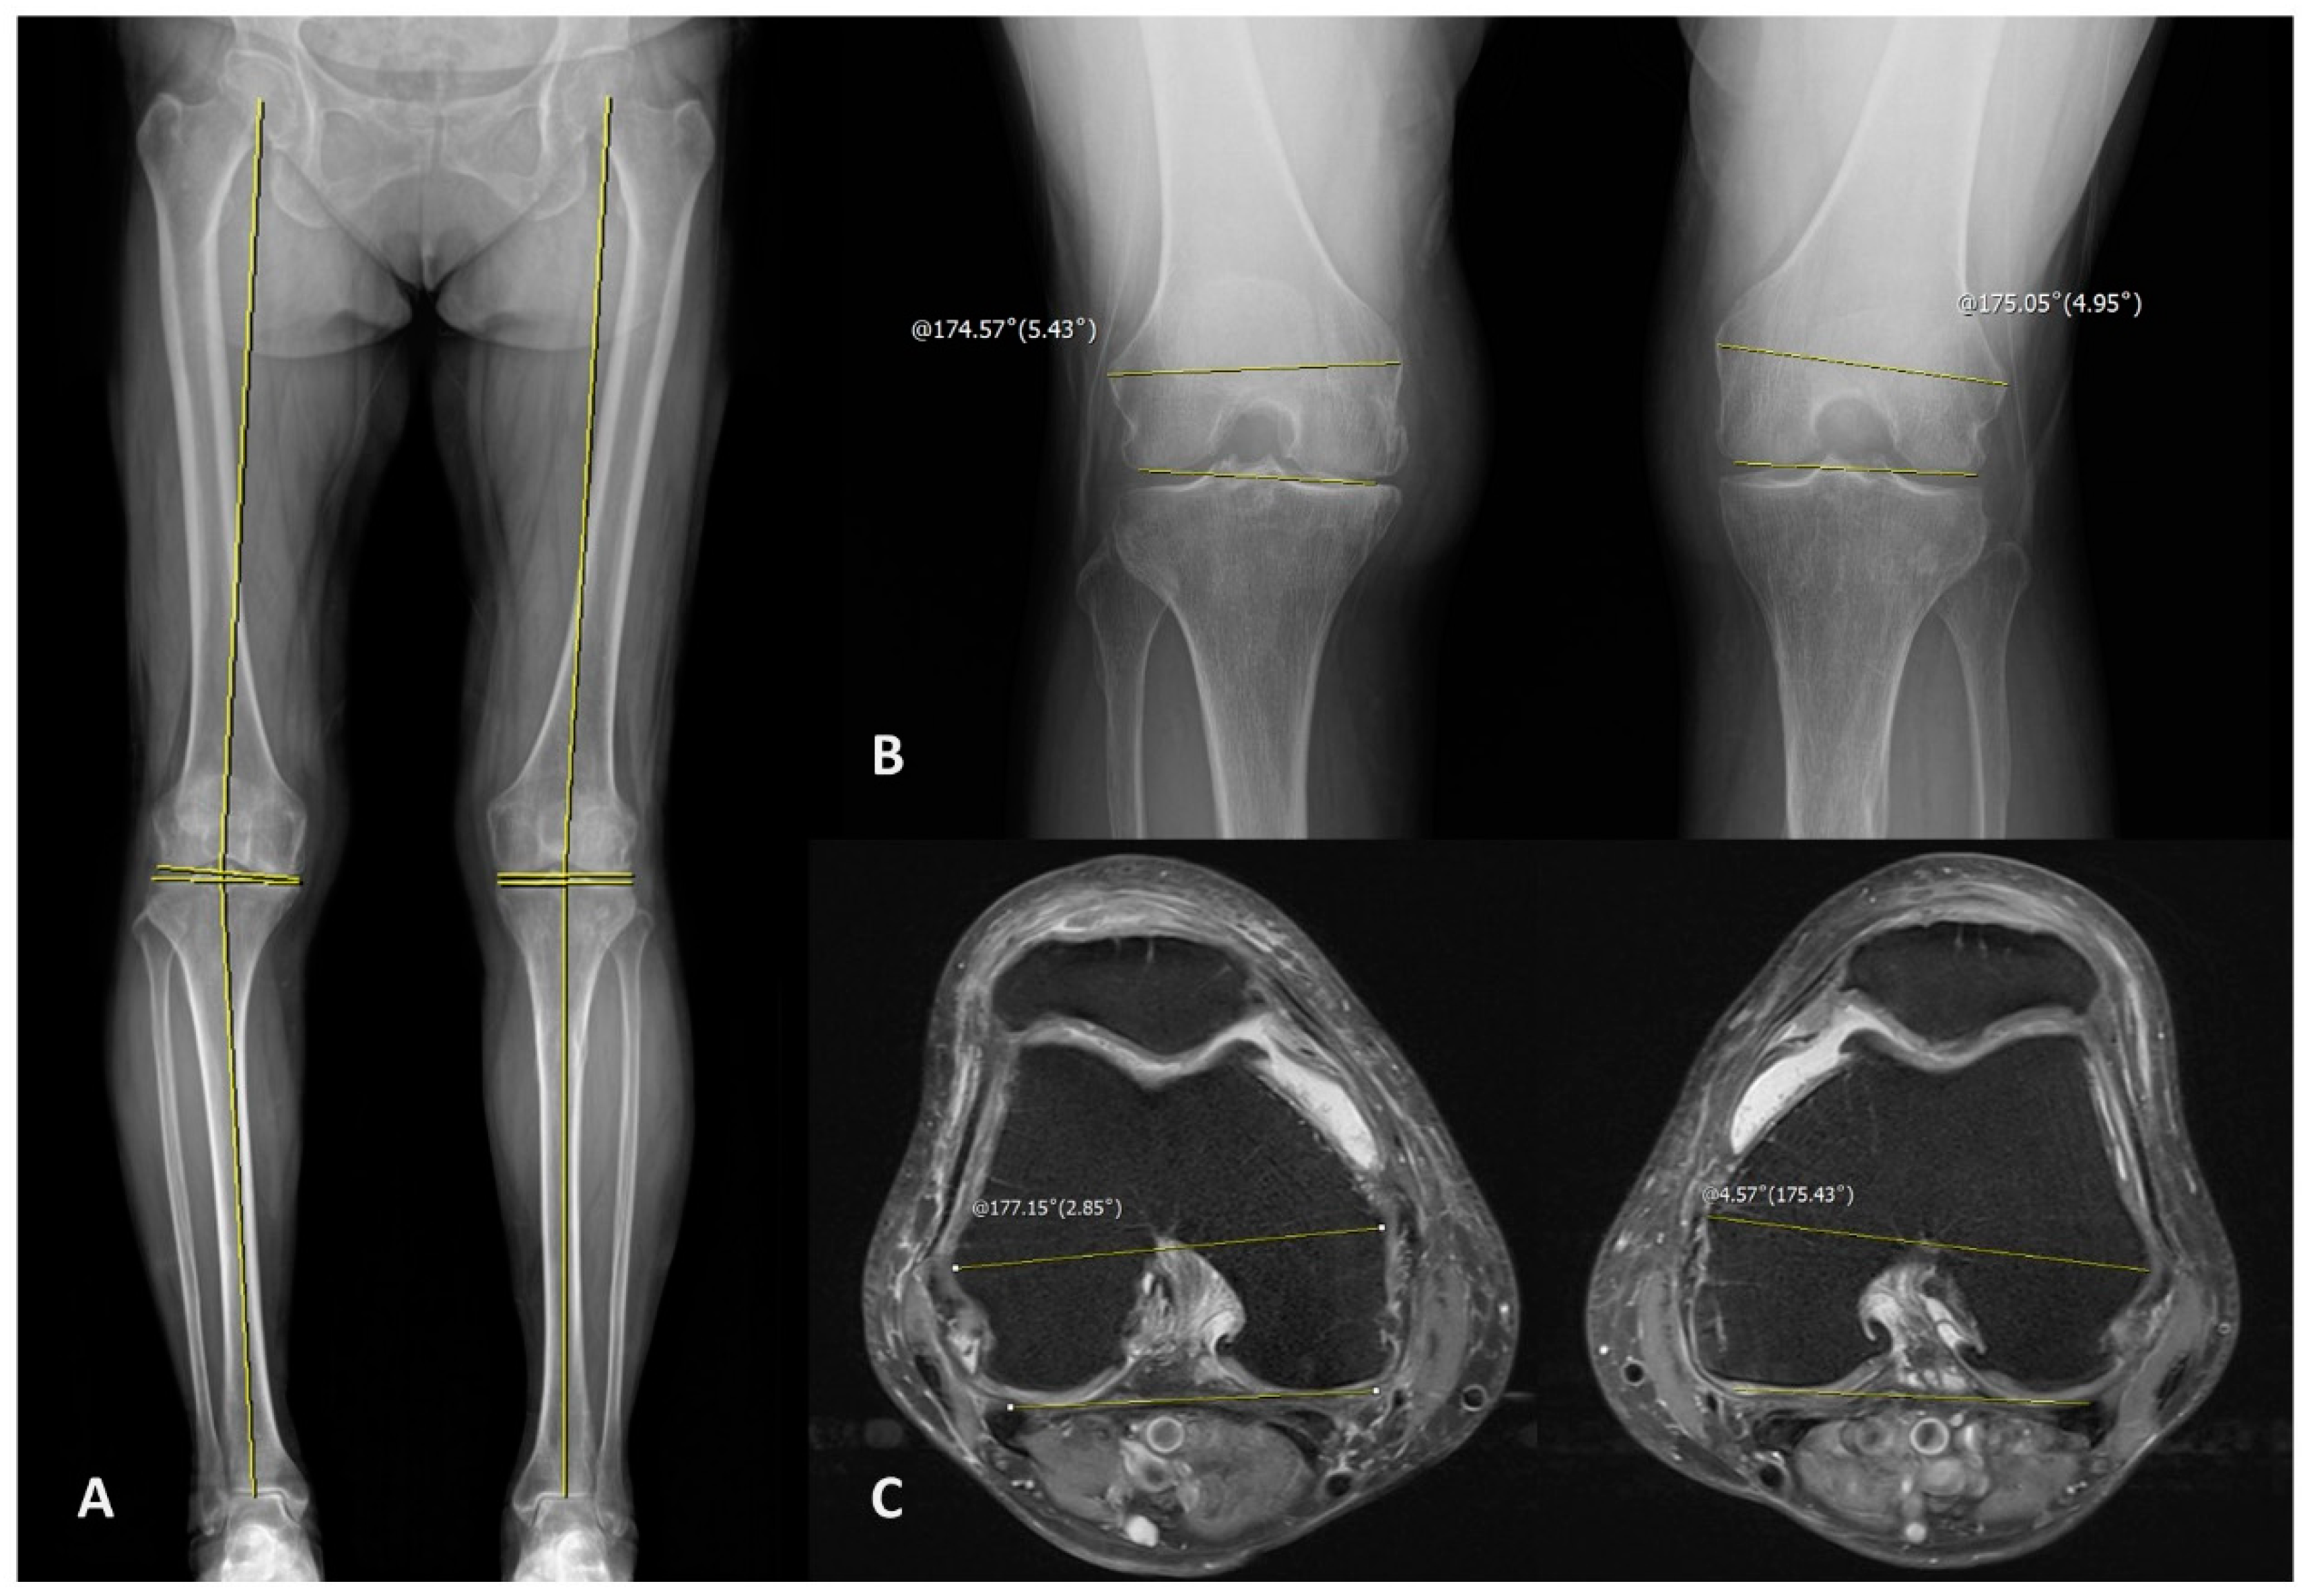

| Characteristics | Numbers |

|---|---|

| Total | Patients: 63/Knee: 121 |

| Gender | Male: 10/Female: 53 |

| Age (mean ± SD) | 72.206 ± 9.587 years |

| Measurements (included numbers) | Mean ± SD (degrees) |

| HKA (n = 121) | 5.934 ± 5.853 (positive value when knee is varus alignment) |

| MPTA (n = 121) | 85.979 ± 2.493 |

| mLDFA (n = 121) | 87.784 ± 2.044 |

| JLCA (n = 121) | 3.748 ± 3.282 (positive value when lateral side is open) |

| MFCA/TEA (n = 121) | 5.630 ± 2.096 (positive value when medial side is open) |

| PCA/TEA (n = 69) | 5.591 ± 2.220 (positive value when medial side is open) |

| PCOA (n = 121) | 107.200 ± 21.254 |